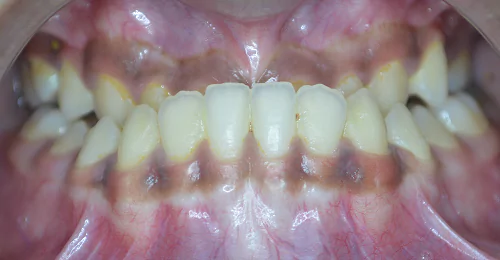

Orthodontic Case – III

(Case Done by Dr. Sonali Deshmukh M.D.S. / Orthodontist )

Deep – II Correction

Pre Treatment